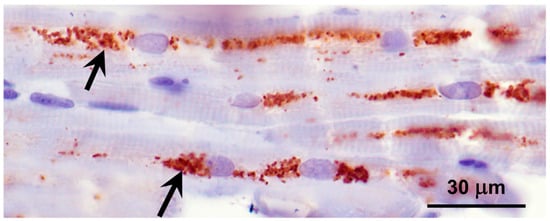

3.2. Microscopic Findings